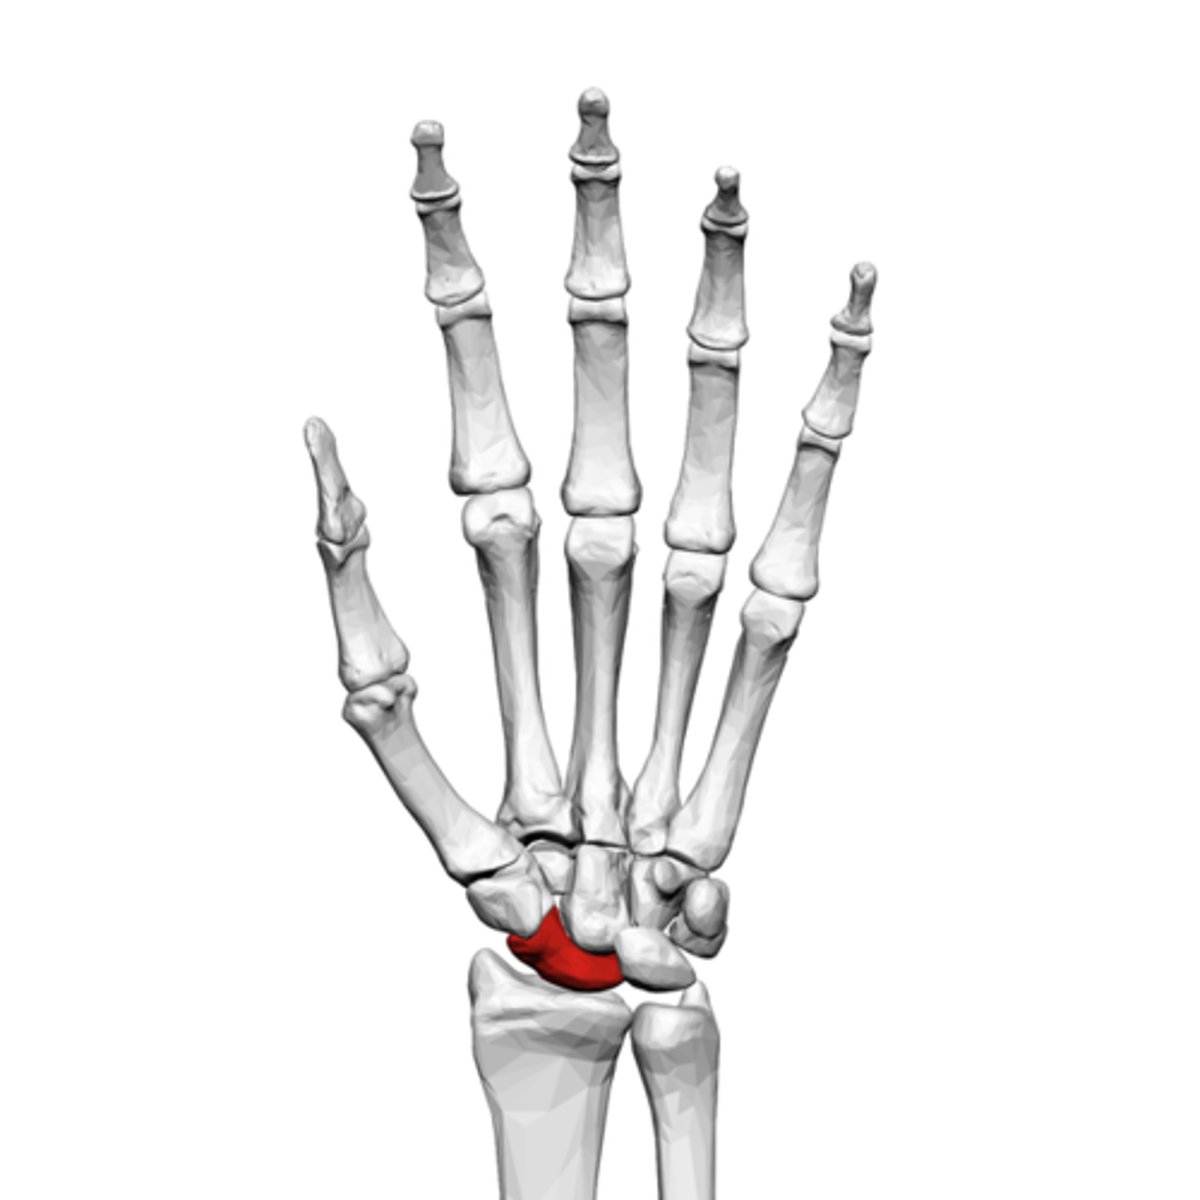

What is the term of the bones highlighted in red?

Lunate